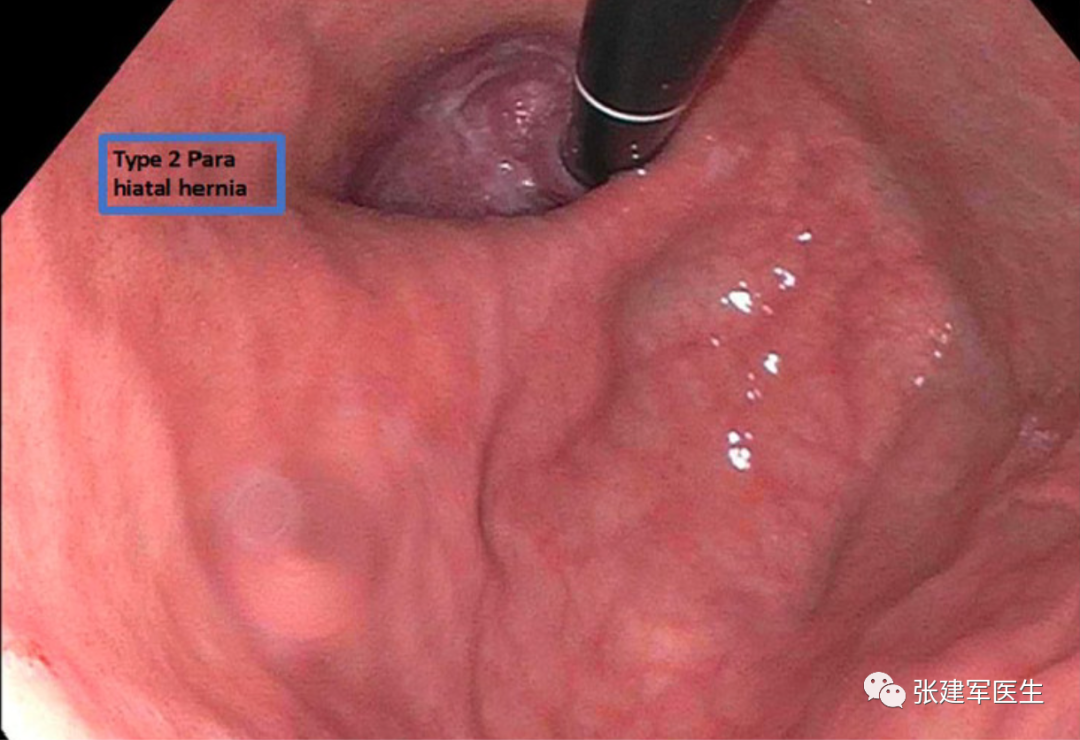

II型(食管旁疝或滚动性食管裂孔疝):胃食管结合部在膈肌下正常解剖位置,胃底或胃体通过胃食管裂孔疝入胸腔,胃底在食管胃结合部上方。

胃十二指肠镜检查

能直观评估食管、胃以及十二指肠粘膜状态,诊断糜烂性食管炎及巴雷特食管(Barrett's esophagus),明确食管裂孔疝的大小及类型,确定食管裂孔疝有无扭转。